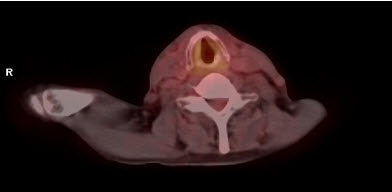

Trước điều trị: hình PET/CT thấy khối u thanh quản (mũi tên vàng) và hạch cổ trái (mũi tên xanh) tăng hấp thu FDG mạnh. SUV u thanh quản = 5,31; SUV hạch cổ = 4,87

Sau hóa xạ trị: u và hạch biến mất, trên hình PET/CT không thấy các tổn thương này nữa.

Hình 1. Bệnh nhân Lê B. L., nam, 66 tuổi. Chẩn đoán: Ung thư thanh quản (ung thư biểu mô tế bào vảy) di căn hạch cổ. Bệnh nhân được chụp PET/CT để đánh giá giai đoạn trước điều trị và mô phỏng lập kế hoạch xạ trị; sau khi được điều trị hóa chất và xạ trị (IMRT) bệnh nhân được chụp lại PET/CT để đánh giá kết quả điều trị. Kết quả cho thấy bệnh đáp ứng hoàn toàn.